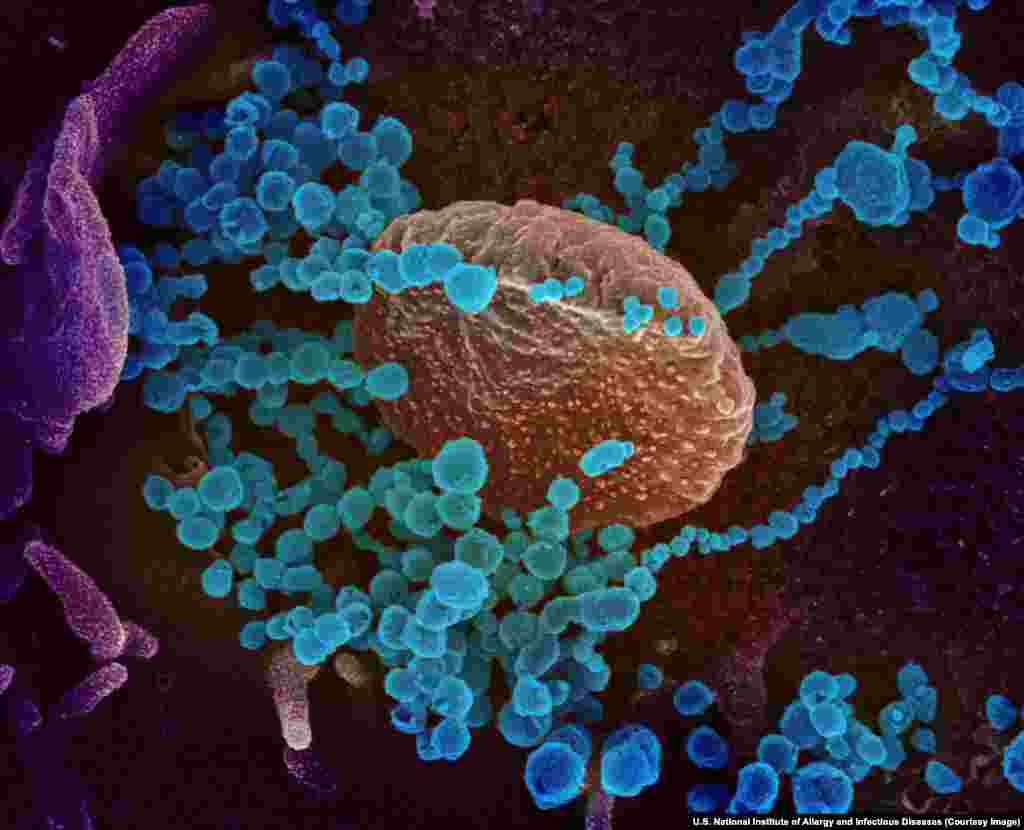

2

Вирионы SARS-CoV-2, разрастающиеся в клетке человеческого организма.

Все фотографии в этой галерее раскрашены с использованием специальных программ, включая Photoshop.

Все фотографии в этой галерее раскрашены с использованием специальных программ, включая Photoshop.